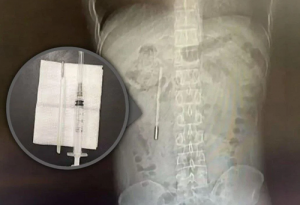

20 лет жил с градусником в животе, потому что боялся всем об этом рассказать

Китаец проглотил ртутный термометр еще в детстве, но решил не говорить об этом родителям. Многие годы его ничего не беспокоило, но спустя 20 лет начались сильные боли в животе. Врачи были в шоке, когда нашли в организме 32-летнего пациента инородный предмет. Градусник удалось извлечь, самое удивительное — он ни капельки не повредился. Пациент тоже чувствует …